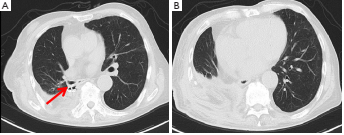

当出现健康肉芽组织,培养未发现胸腔感染时,行肌瓣转位术。术中切取背阔肌前锯肌20cm×15cm复合带蒂肌瓣。将联合皮瓣的尖端缝合并固定在中下纵隔,其余部分移位以几乎完全消除脓胸腔,同时转移部分骶棘肌以填充残余间隙(图2A)。患者于术后第58天出院(图2B)。术后胸部CT扫描显示BPF和脓胸腔已被成功清除(图3)。患者一直保持健康,在5个月的随访中没有明显的脓胸瘘复发。

图3. 术后5个月的胸部CT扫描显示成功地用Amplatzer装置(箭头)和带蒂肌瓣封堵了BPF和脓胸腔